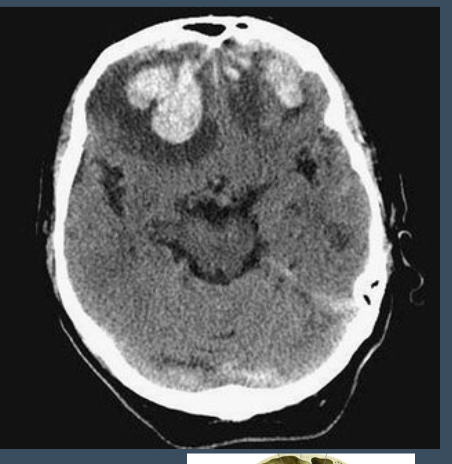

What type of injury is shown in the provided image?

Intracerebral hemorrhage (contusion)

Bony areas

YES - surgery is indicated